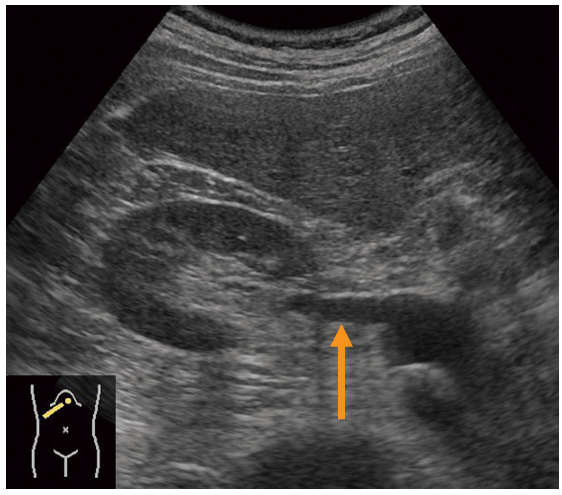

健常成人の右肋弓下走査の超音波像を示す。

矢印で示すのはどれか。

右の腹部大動脈から分岐して腎臓へと伸びているので右腎静脈と考えられる

答え 4